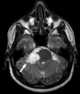

Arterial spasm

Vasospasm refers to a condition in which an arterial spasm leads to vasoconstriction. This can lead to tissue ischemia and tissue death (necrosis). [Source: Wikipedia ]